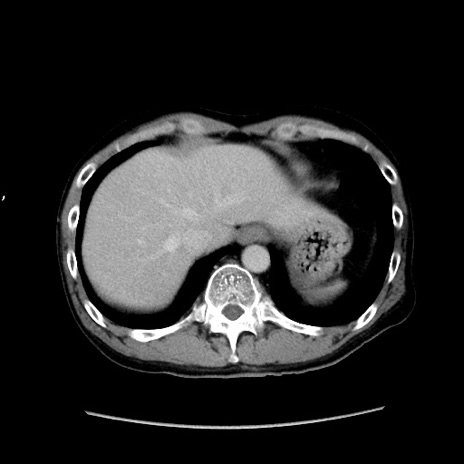

症例37(横断像)

【症例】40歳代 男性

【主訴】腹痛

【現病歴】4時間ほど前に電車に乗車中に臍部上より腹痛出現。徐々に増悪し起立困難となり、救急外来受診。生ものは数日食べていない。今朝お雑煮を食べた。

【身体所見】BT 36.8℃、BP 117/84mmHg、HR 91/min、SpO2 97%、苦悶様、腹部:臍上部広範囲圧痛あり、反跳痛±

【データ】WBC 8100、CRP 0.03